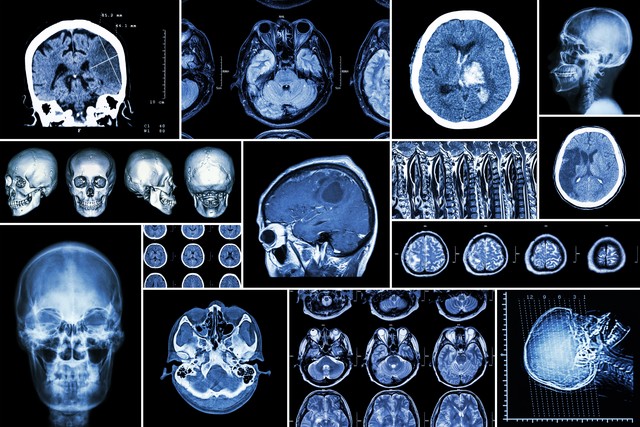

脑梗这个病,其实致死率极低,恐怖的是它的复发率以及令患者相当痛苦、难受的后遗症。

脑梗发病以后,患者或多或少都会留下,或上肢或下肢或语言的后遗症,只不过有的不显著于外而已。

脑梗患者受梗塞部位、是否及时溶栓、溶栓效果、梗塞面积等一系列因素影响,后遗症有重有轻。都面临康复期到底是多久呢,这个疑问?